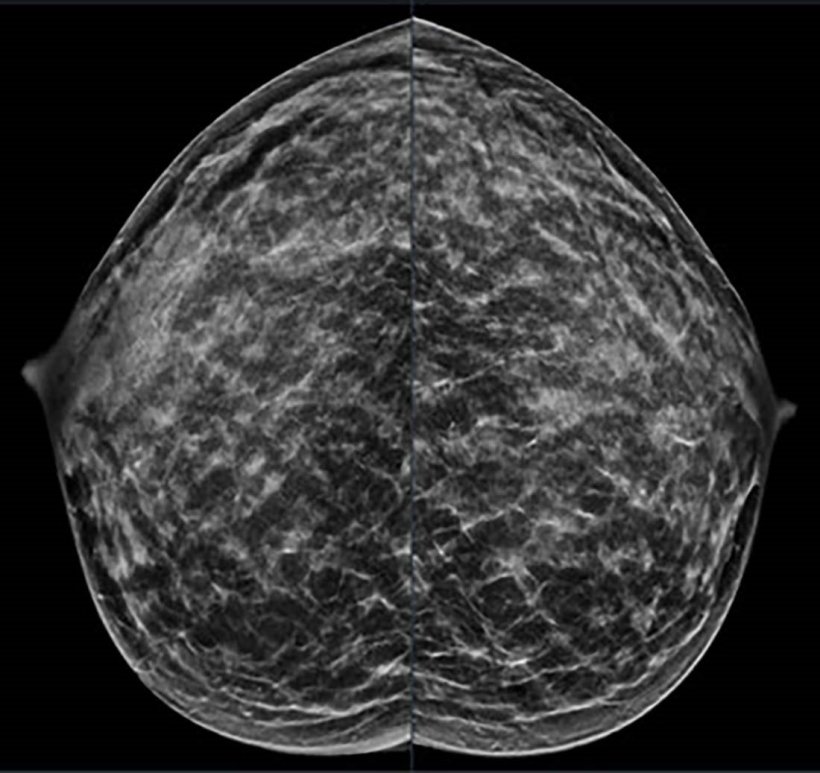

Image credit: Stamatia Destounis, M.D., and RSNA

A study of data from seven outpatient facilities in the New York region found that 20-24% of all the breast cancers diagnosed during an 11-year period were found in women age 18 to 49, according to new research.

A total of 1,799 breast cancers were diagnosed in 1,290 women, aged 18 to 49. Annual breast cancer diagnoses in this group ranged from 145 to 196, with a mean age at diagnosis of 42.6 years (range 23-49). Of these, 731 (41%) were detected on screening and 1,068 (59%) on diagnostic evaluation. There were 1,451 invasive cancer cases (80.7%), and 347 (19.3%) non-invasive cancer cases. “Most of these cancers were invasive, meaning they could spread beyond the breast, and many were aggressive types—especially in women under 40,” Dr. Destounis said. “Some were ‘triple-negative,’ a form of breast cancer that is harder to treat because it doesn’t respond to common hormone-based therapies.”